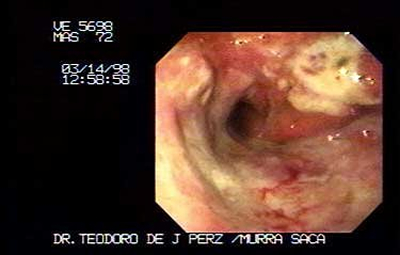

Paciente Masculino de 72 años:

Quien ha tenido larga historia y tratamientos multiples para dispepsia inicio sintomatología obstructiva por lo que consultan con medico general, quien inmediatamente me localiza vía telefónica para que le practicáramos este estudio. Extenso Carcinoma Gástrico que obstruye antro e infiltra extensamente el cuerpo y fondo.